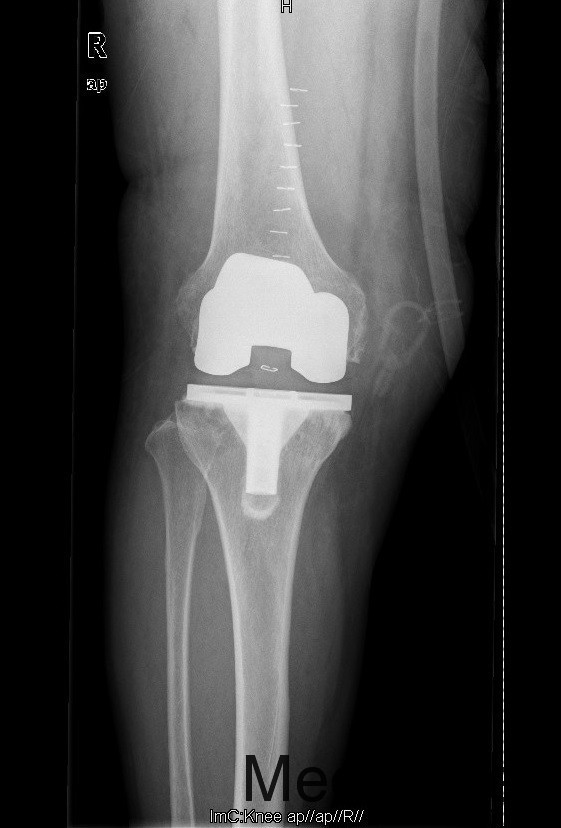

查体:步态跛行,双膝屈曲畸形,左膝外翻、右膝内翻畸形,双膝内外侧关节间隙及髌股关节间隙压痛明显,右侧重,右膝内翻:5°,右膝屈70°,伸-10°;左膝:屈曲:100°,伸:-5°,外翻:20°,双膝主被动屈伸活动时疼痛,双膝髌下摩擦音(+)。 辅助检查:右膝关节间隙狭窄,软骨下骨硬化,髌股关节间隙消失,左膝关节间隙狭窄,软骨下骨硬化,髌股关节间隙狭窄,双膝髌骨、股骨、胫骨周围大量骨赘形成,关节腔内均可见游离体。

诊断:1.双膝重度骨关节炎继发右膝屈曲内翻畸形,左膝屈曲外翻畸形(Krackow Ⅰ型)2.高血压病(3级 极高危) 治疗:积极行术前准备,待血压等稳定后于全麻下行右侧全膝关节置换术,术后常规治疗,并鼓励其锻炼。